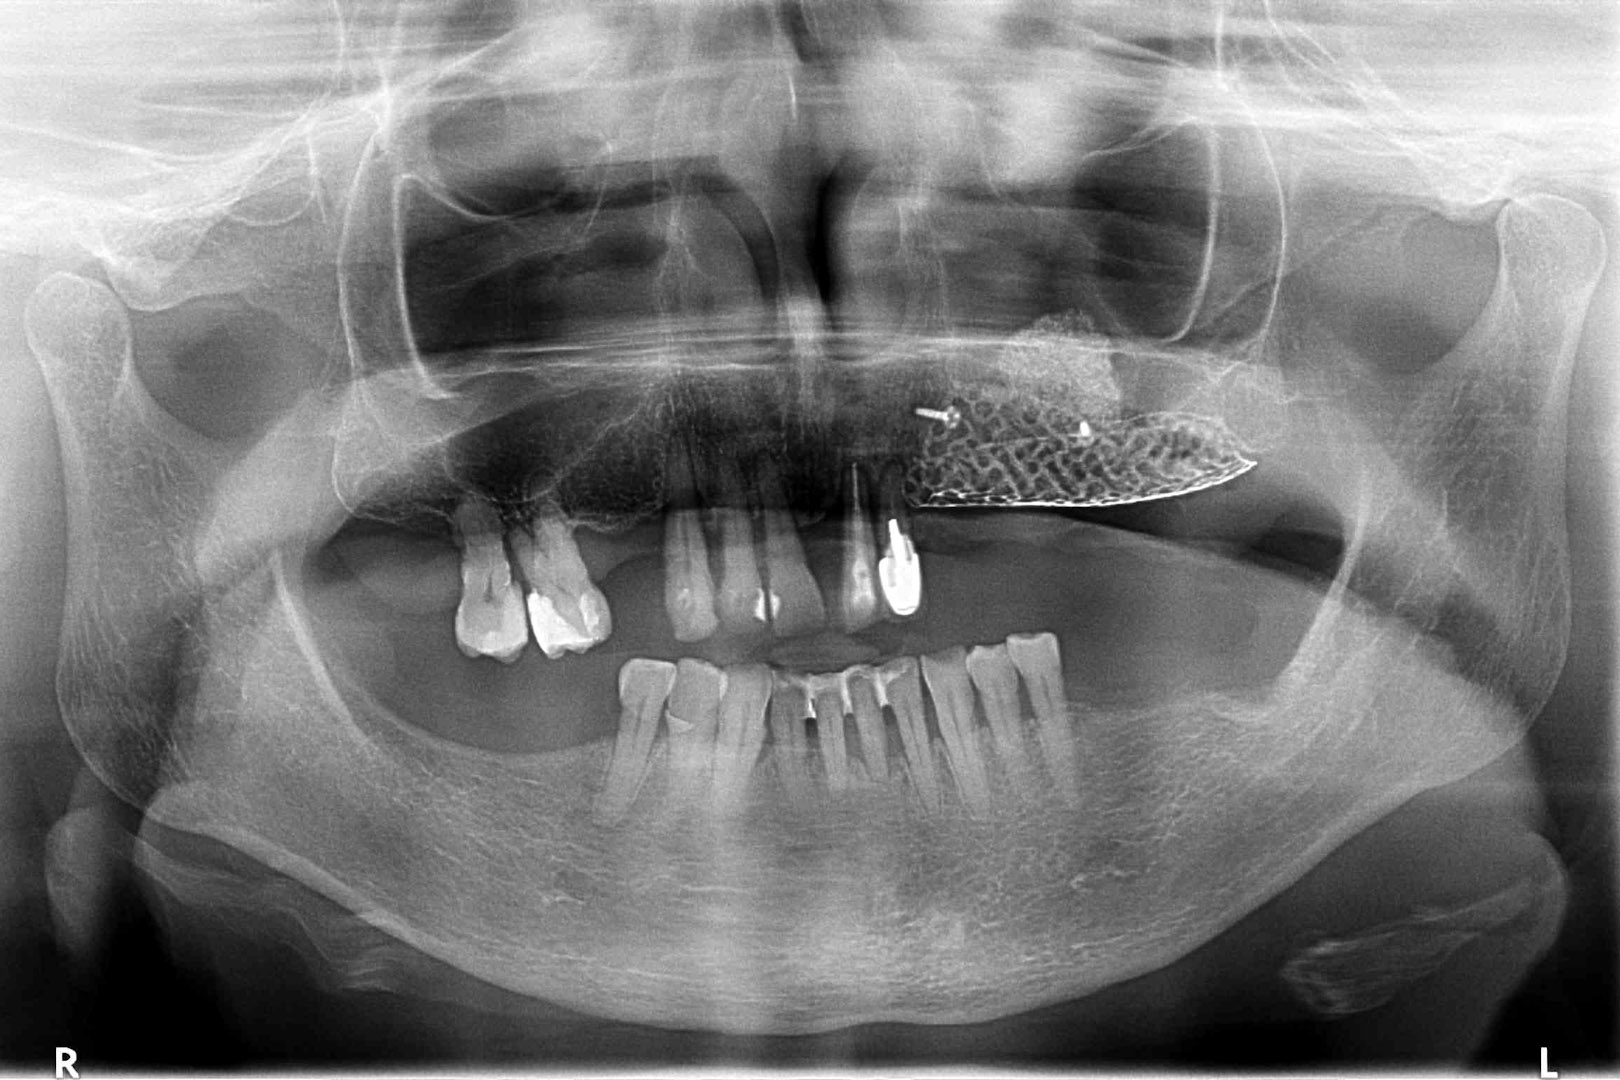

Przed podjęciem leczenia należy określić stopień zaniku kości szczęk oraz żuchwy. W tym celu przeprowadza się badanie kliniczne oraz odpowiednią diagnostykę obrazową pacjenta. Uwzględnia ona zdjęcie panoramiczne OPG jako podstawę dwuwymiarowego obrazowania podłoża kostnego oraz możliwe jest badanie tomograficzne CT lub bardziej precyzyjna tomografia stożkowa CBCT. Opcjonalnie wykorzystywana diagnostycznie tomografia pozwala na bardziej wnikliwą ocenę stopnia zaniku kości w trójwymiarowym, przestrzennym obrazie.

REKONSTRUKCJA KOSTNA TRÓJWYMIAROWYCH UBYTKÓW PRZY UŻYCIU ZEWNĘTRZNYCH STABILIZATORÓW LUB NIERESORBOWALNYCH MEMBRAN, NADAJĄCYCH FIZJOLOGICZNY KSZTAŁT ODBUDOWIE KOŚCI

Technika ma wiele zalet, ponieważ przy użyciu nowatorskich materiałów i innowacyjnej technologii jako pierwsza umożliwiła odbudowę kostną wyrostka zębodołowego w zadanej formie i kształcie. Natomiast istotną wadą metody są występujące obnażenia membran podczas trwania procesu regeneracyjnego, które bywają przyczyną stanów zapalnych, zmuszających do przerwania procesu odbudowy kostnej i usunięcia błony. Sytuacja brzeżnego obnażenia błony wymaga zwykle jej usunięcia, natomiast centralne jej odsłonięcie rokuje kontynuację leczenia pod ścisłym rygorem częstych kontroli oraz wykonywania zabiegów higienizacyjnych.

To kolejna metoda umożliwiająca precyzyjną odbudowę zadanego kształtu tkanki kostnej przy użyciu standardowych materiałów kościotwórczych, kości własnej lub PRF oraz zewnętrznego rusztowania w postaci siatki z biozgodnego stopu tytanu. Siatka jest indywidualnie projektowana w technologii CAD CAM i następnie drukowana dla konkretnego przypadku.

Dotychczas stosowane stabilizatory zewnętrzne w formie siatek tytanowych używane do regeneracji kostnej lub w zabiegach odtwórczych w chirurgii szczękowo-twarzowej uwzględniały materiały ręcznie doginane i formowane podczas zabiegu operacyjnego. Zastosowanie technologii CAD CAM dla potrzeb druku materiałów przeznaczonych do indywidualnej rekonstrukcji kostnej znacznie poprawiło precyzję i jakość uzyskiwanych efektów. Wdrożenie biozgodnych stopów tytanu do druku siatek zdecydowanie ograniczyło odsetek powikłań zapalnych.

Siatki stanowią stabilną obudowę – ograniczenie nadające kształt regenerowanej kości przy użyciu upakowanego pod nią materiału. Utrzymują i stabilizują rozdrobniony granulat kościotwórczy, co jest warunkiem prawidłowego procesu gojenia, jednocześnie nadając anatomiczny kształt i zakres odbudowie kostnej sprzed jej zaniku.

Precyzja projektu druku siatki bazuje na dokładności odwzorowania kształtu kości w stożkowej tomografii komputerowej CBCT, co zapewnia ich dobre przyleganie do podłoża kostnego oraz ogranicza powstawanie powikłań w postaci obnażania się siatek.

Precyzja projektu oraz materiał, z którego wykonana jest siatka (biozgodny stop tytanu), powodują, że obnażenie się siatki nie zaburza procesu gojenia i regeneracji kostnej. Wymaga jedynie większej ilości kontroli pozabiegowych oraz wzmaga czujność higieniczną zarówno ze strony lekarza, jak i pacjenta.

Ten rodzaj odbudowy kostnej stosowany jest w sytuacjach złożonych, trójwymiarowych 3D ubytków kości, przy których standardowe metody odbudowy są niewystarczające. Ilość kości, którą możemy uzyskać, stosując tę metodę, to nawet kilka centymetrów sześciennych.

Metoda rekonstrukcji kostnej w oparciu o indywidualnie drukowane siatki z tytanu dla implantacji wszczepów śródkostnych stosowana jest najczęściej jako dwuetapowa. W pierwszym etapie odbudowywana jest kość, natomiast implanty wszczepiane są po okresie 4–6 miesięcy. Na wgojenie implantów oczekujemy od 4 do 6 miesięcy w zależności od miejsca ich lokalizacji. Siatka tytanowa po spełnieniu swojej funkcji rusztowania dla odbudowującej się kości jest następnie usuwana w dniu wszczepienia implantu. Jeżeli kość spełnia odpowiednie warunki, istnieje możliwość zastosowania modyfikacji siatki tytanowej, która umożliwia jednoczesne wprowadzenie implantów wraz z odbudową kostną. Wariant ten skraca czas od pierwszego zabiegu do wykonania gotowych koron protetycznych na wprowadzonych implantach.

WYBRANE PRZYPADKI REKONSTRUKCJI 3D PRZY UŻYCIU SIATEK TYTANOWYCH REOSS